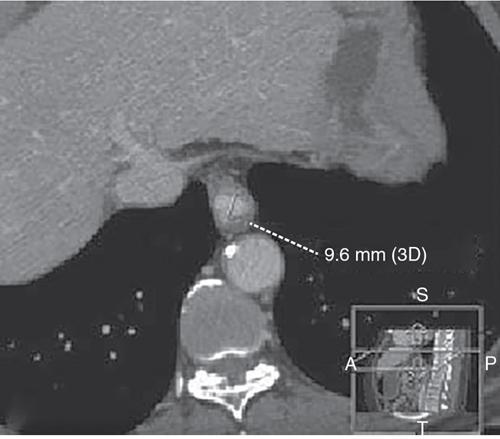

• Diameter of the oesophagus (Fig. 7.3.3).

• Measured on axial CT images.

• Diameter up to 15 mm is considered normal.

• Any measurement 20 mm or more is abnormal.

Fig. 7.3.3 Measuring diameter of the oesophagus on axial CT image.